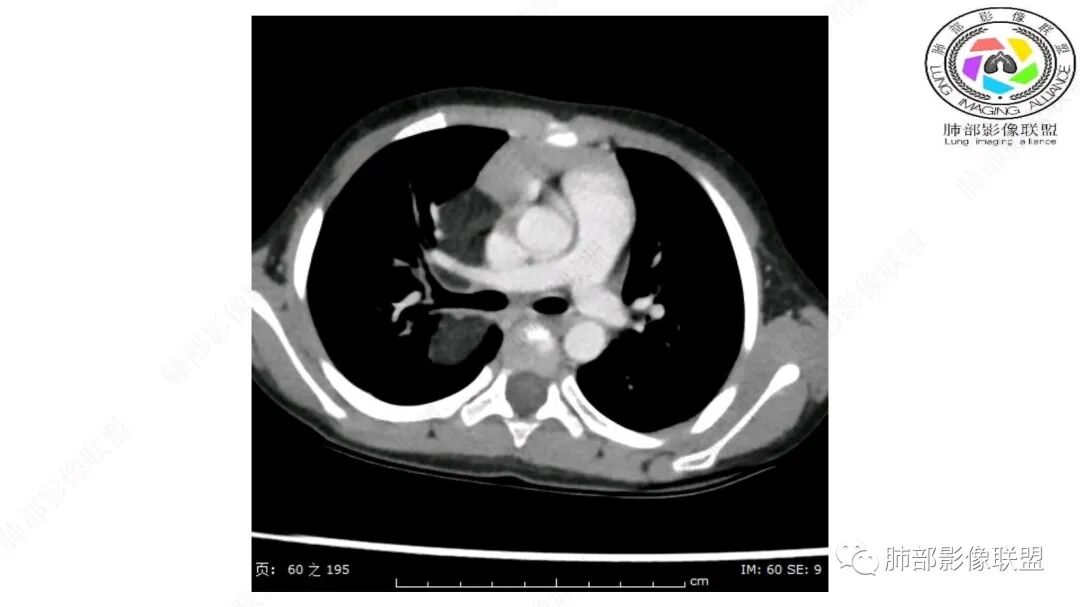

右上纵隔混杂密度肿块,边缘光整,与纵隔分界清,其内多发脂肪密度,增强无明显强化,其内血管穿行,考虑纵隔脂肪母细胞瘤,鉴别畸胎瘤,脂肪肉瘤。

三岁小儿,右侧纵隔巨大脂肪密度肿块,肺动脉穿行其中,密度欠均匀,未见明确实性成分,纵隔脂肪母细胞瘤,冬眠瘤鉴别纵隔脂肪增多症(多弥漫对称)。

病灶属于交界区,主体位于肺内,占位效应明显,前方突入胸壁,胸腺受压变形,胸膜显示欠清楚;病灶包绕上叶肺动脉;似乎有体动脉供血。符合肺内的点:包绕上叶肺动脉分支;符合纵隔的点:前方似乎突入胸壁,与胸腺关系比较密切,但是与上腔静脉的关系提示病灶不支持纵隔来源,前纵隔的常规会将上腔静脉受压后移、外移,这是不符合的。

内部血管明显,部分病灶密度增高,单纯脂肪瘤不支持。可惜的是:没有提供CT值:是否强化?如果强化,警惕恶性;胸腺肯定不符合,胸腺会将上腔静脉朝后推移。

2.肺动脉穿行也许是肺内来源最重要支持点!